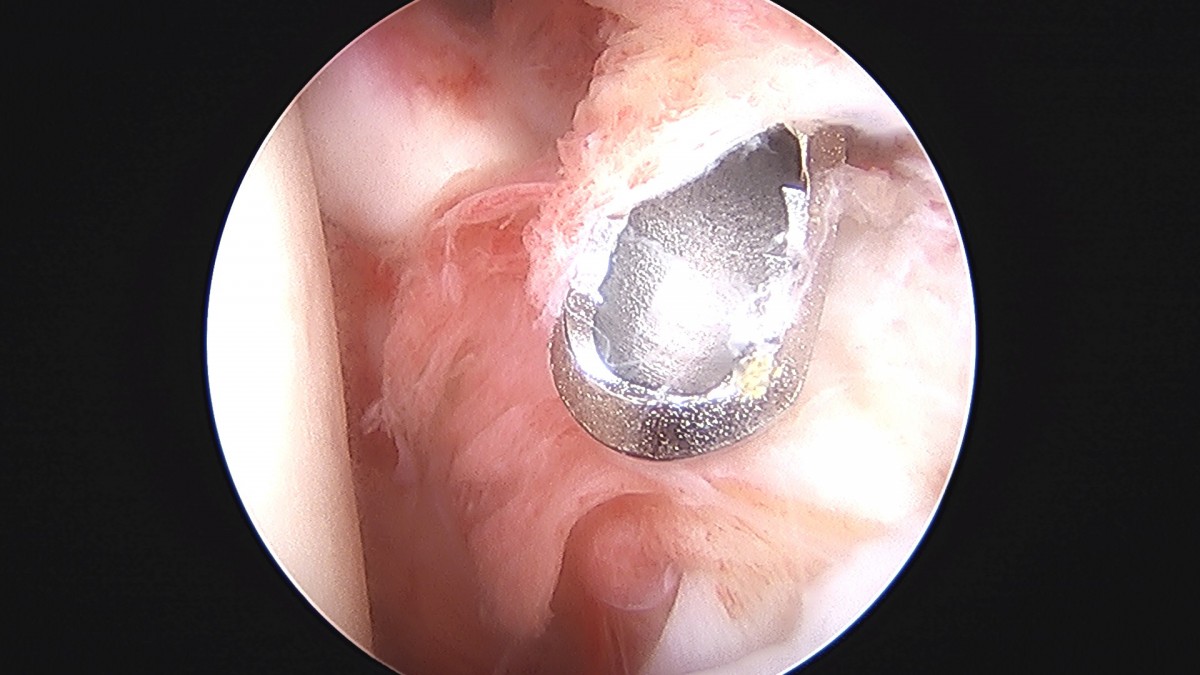

정지영원장님 어깨 관절낭 이완술 및 석회제거술 박설O 환자

작성자 최고관리자 댓글 0건 조회 732회 작성일 25-09-16 16:59